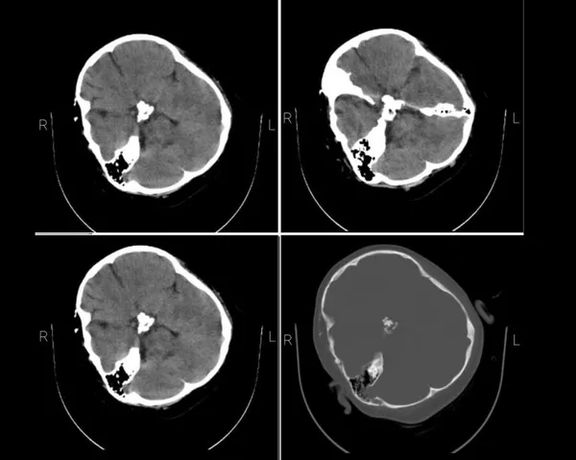

Iran International obtained Amini’s brain CT scan from hospital sources in September that shows serious injuries to her skull. Hospital staff also confirmed that she was in a coma upon arrival. Fars news agency affiliated with the Revolutionary Guard confirmed that the CT scan belonged to Amini. Moreover, her photos in the hospital show her bleeding from the right ear, a definite sign of brain injury.

Mahsa Amini's brain CT scan obtained by Iran International, September 2022

Mahsa Amini's brain CT scan obtained by Iran International

"Due to the ineffective cardio-respiratory resuscitation in the first critical minutes, she suffered severe hypoxia and as a result brain damage," the coroner’s report said.